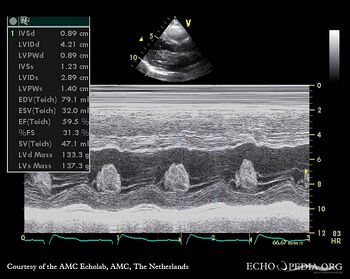

Giant myxoma in left atrium

M-Mode through mitral valve